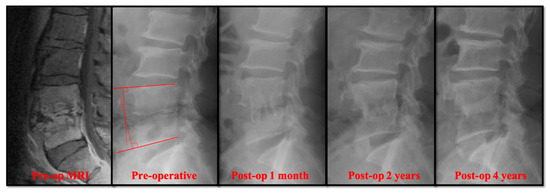

Figure 1. A 55-year-old man presented with severe pain in the lower back and was diagnosed with L4–L5 Escherichia coli infection. Four years after the traditional anterior open surgery, bony fusion was seen in the infected L4–L5 segment. The sagittal angle was measured by the angle of the perpendicular lines from the upper and the lower endplates.

Radiographically, the primary correction gain after surgery was slightly higher in the open surgery group (Table 2). However, there was no significant difference in the change of sagittal profile, including primary correction gain (2.20° ± 2.91° versus 3.04° ± 3.65°), correction loss (2.41° ± 3.92° versus 3.68° ± 2.76°), and actual correction gain/loss (−0.21° ± 5.59° versus −0.64° ± 5.01°). In the follow-up radiographs, the successful bony fusions of the infected segments appeared in most of the anterior open surgery cases (Figure 1). A successful bone fusion was determined by continuously trabecular bony bridging between vertebrae and bone graft. There was no change in the sagittal angle of the targeted spinal segment between flexion-extension dynamic plain radiographic views because not every patient would consent to computerized tomography scans. Twenty-six out of 30 (86.7%) open surgery patients showed solid fusion at two years for the follow up. Nevertheless, 8 patients had obvious subsidence of the bone grafts due to damaged endplates in the early periods. Conversely, the destructive endplates of the infected segments became sclerotic, although decreased intervertebral disc height and local kyphosis were observed after successful treatment in the PEDD group (Figure 2). However, the motion of these infected spinal segments was still preserved after successful PEDD treatment. In the longer follow up, two patients showed spontaneous fusion in the PEDD group (Figure 2).